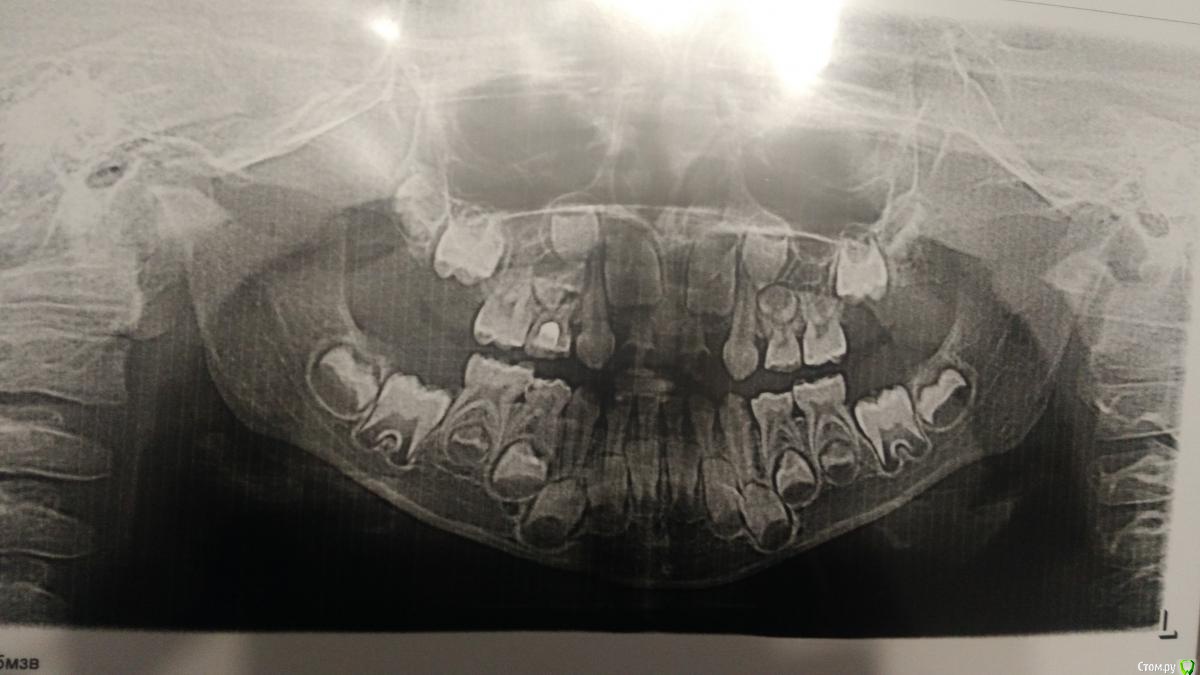

ИринаДементьева Опубликовано 11 сентября, 2018 Поделиться Опубликовано 11 сентября, 2018 Уважаемые доктора, посмотрите какие зубы постоянные отсутствуют в зачатках? Ссылка на комментарий

St. Опубликовано 11 сентября, 2018 Поделиться Опубликовано 11 сентября, 2018 Добрый день. Отсутствуют зачатки обоих верхних 2, возможно еще правой 5 ( но там пока не совсем хорошо видно на данном этапе формирования) Ссылка на комментарий

ИринаДементьева Опубликовано 13 сентября, 2018 Автор Поделиться Опубликовано 13 сентября, 2018 Добрый день. Отсутствуют зачатки обоих верхних 2, возможно еще правой 5 ( но там пока не совсем хорошо видно на данном этапе формирования)Сыну сейчас 5,10, через какое время снова лучше сделать? Ссылка на комментарий

St. Опубликовано 13 сентября, 2018 Поделиться Опубликовано 13 сентября, 2018 Наблюдайтесь у детского стоматолога в плане гигиены и лечения кариеса по необходимости. Как часто бывать на осмотрах скажет ваш доктор, стандартный промежуток 3-6 мес обычно.Снимок раньше чем через год смысла делать нет.В любом случае в плане отсутствующих зубов пока что ждать Ссылка на комментарий